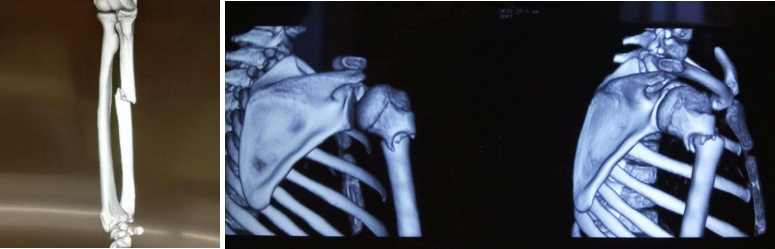

我们这里也有一个案例:我们这个当事人是一个企业家,他与一名老年女性发生了拉扯,在拉扯的过程当中,这名老年女性说手痛、手腕骨折,接着就报警送医。送医去检查的时候,还真的是发现它存在尺骨远端骨折和桡骨茎突骨折,四肢长骨两处骨折,就够得上轻伤一级,可以说是非常严重的。

受害人她自己坚称就是在拉扯的这个过程当中造成骨折,而且当时也是有视频证明,他们只是发生了拉扯。在公安机关进行鉴定的时候,就直接给他认定了一个轻伤一级,但是损伤方式也就是损伤机制没有进行分析。

我们接受委托之后,就发现有一个非常严重的问题,就是她虽然是两处骨折,但是在手腕这个部位,骨折存在压缩的表现,结合这个压缩的表现,我们就认为拉扯不可能形成的。我们也请专家进行了分析,专家一看这就是典型的一个跌倒之后的撑地伤。

后来我们就对这个致伤方式进行了分析,因为在公安阶段我们是只看到了鉴定意见,其他的内容我们看不到,所以我们就倒推,通过这个《人体损伤程度鉴定标准》轻伤一级的相关条款来倒推到底可能是哪种方式,并进行了论证。

后来我们跟公安机关的承办人员去交流,他们也没有引起重视,依然移送了检察院。到了检察院之后,我们再去跟公诉人进行交流的时候,他们非常重视。接着他们就请他们的法医进行技术性证据的审查,在审查的时候发现他们的观点跟我们的观点是一致的,认为这是跌倒之后的撑地伤,显然不是拉扯造成的。最后检察院作出不起诉决定。